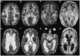

Leukoencephalopathy - thalamus and brainstem anomalies - high lactate

Brainstem anomaly

High lactate

Thalamus anomaly